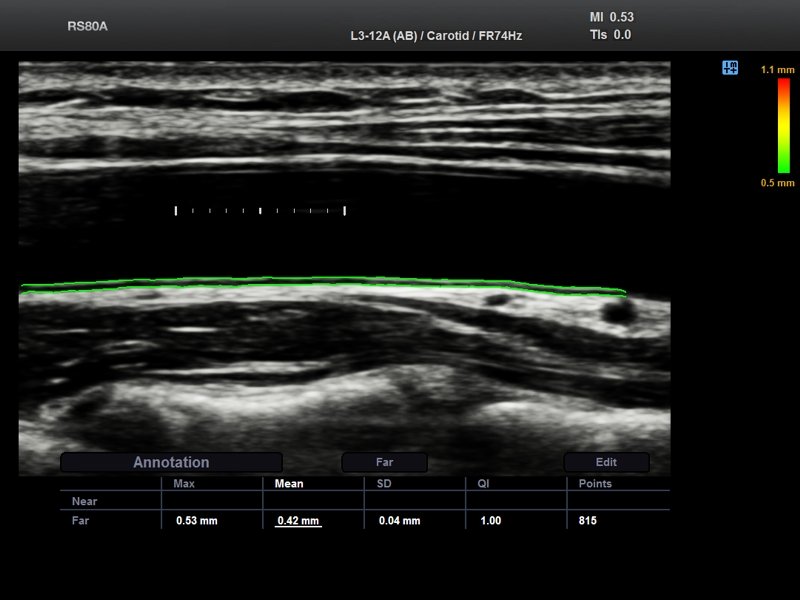

Common carotid artery, Auto IMT (echogramm №702)

[RU] Ultrasound image №702: Common carotid artery (CCA) - automatic calculation of Intima Media Thickness.